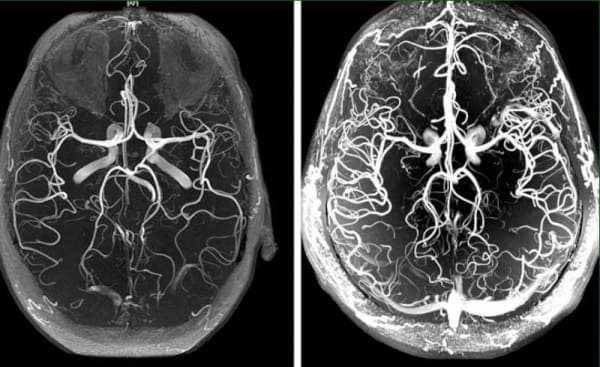

Cerebrovaskulární angiodystonie – je patologický stav, při kterém je narušen cévní tonus a normální průtok krve v mozkové tkáni. V tomto článku se dočtete o jejích příčinách, mechanismech a příznacích, kvůli kterým je čas se znepokojovat. A také o děsivých komplikacích tohoto zákeřného onemocnění a o moderním dostupném přístupu k léčbě.

"Cerebrální vaskulární angiodystonie je počátečním příznakem celkového ""znečištění"" cév cholesterolem - aterosklerózy. Mozkové cévy jsou nejjemnější a nejtenčí, takže trpí jako první."

"Čím více nečistot se v cévách hromadí, tím závažnější jsou následky. Mírné znečištění mozkových cév má obvykle za následek mrtvici a úplné nebo částečné ochrnutí."

"Nešťastné cévy již trpí nahromaděnými ""vrstvami"" cholesterolu, které narušují epitelové stěny a způsobují jejich ztenčení. A vazodilatátory cévy roztahují, čímž dochází k nadměrnému roztažení stěn. Pokud v tomto okamžiku céva praskne, dojde k mrtvici."